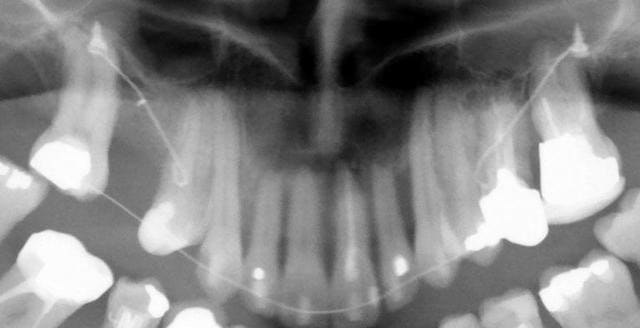

A trois mois (photos f0), remplacement du fil élastique par un fil NiTi enfilé dans les lumières de composite. Un chaînette élastomérique continue la traction.

A six mois (photos f1, f2 et f3), résultats à ce stade et panoramique de contrôle.

la dernière, comparaison à 6 mois.